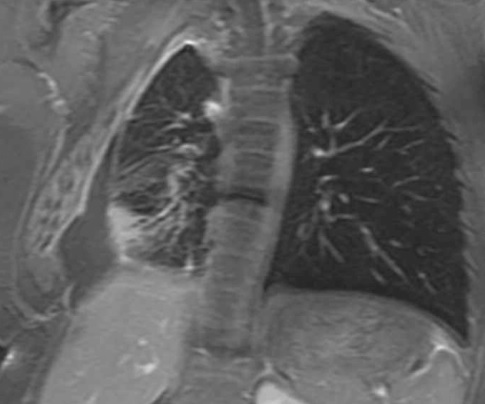

Image radiologique IRM normale de plèvre

(radioanatomie ) : L'IRM a un

rôle relativement limité

dans l'imagerie de la plevre pulmonaire, .le

signal de la plevre est spontanément faible (densité

protonique) , elle considérée comme un examen de seconde

intention après l'examen tomodensitométrique . Mais

dans quelque cas elle est préférée à la tomodensitométrie

dans des circonstances spécifiques, telles que l'évaluation

de .. des plèvres pathologique : lesion inflammatoire

epanchement pleurale , tumeur de la paroie invasive ou

sequnce de diffusion des mésothéliomes...( voir sur la

chapitre semiologie et pathologie radiologique du poumon )

et elle est en vue facile sur les coupe ponderee sur T1 , T2

, FatSat

Image radiologique IRM normale du

thorax en coupe coronal ponderee sur T2 . Image de

la plevre est mal de interpreter |